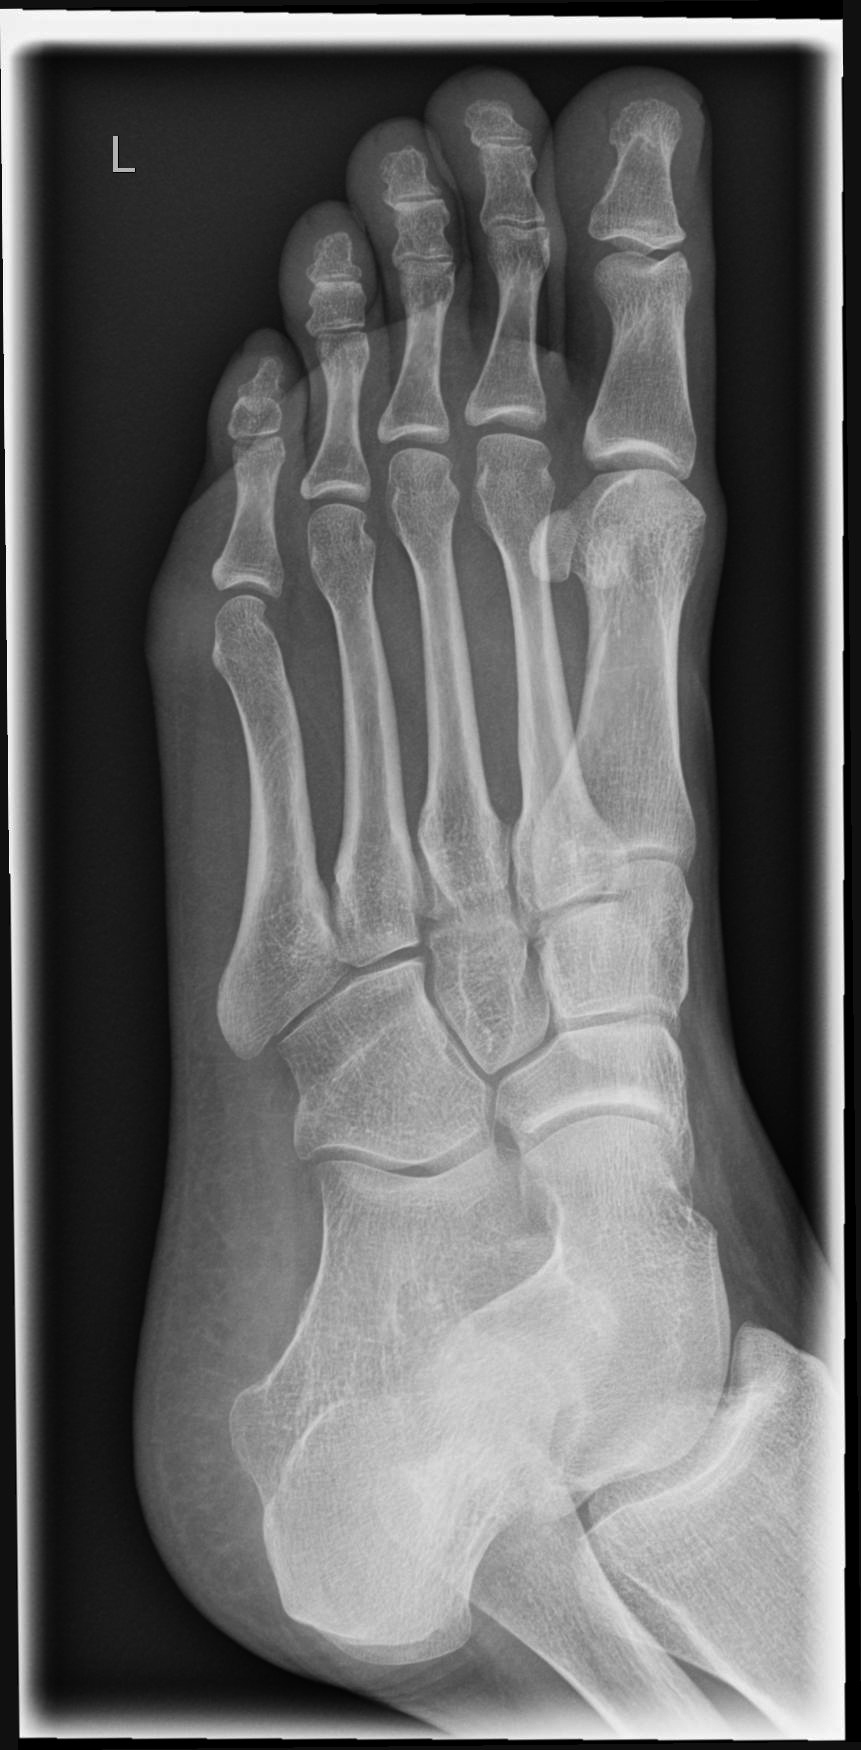

Fuß dorso-plantar (a.-p.) 1. Ebene

Fraktur, entzündliche und degenerative Veränderungen

sitzend/ liegend auf Tisch

Knie gebeugt und Fuß aufgestellt

Fußsohle liegt plan auf Bildempfänger

senkrecht auf Objektmitte

proximal bis einschließlich Malleolus lateralis

Möglichst überlagerungsfreie Aufnahme der Mittelfußknochen, sodass die Fußwurzel-Mittelfuß- Gelenke gut beurteilbar sind.